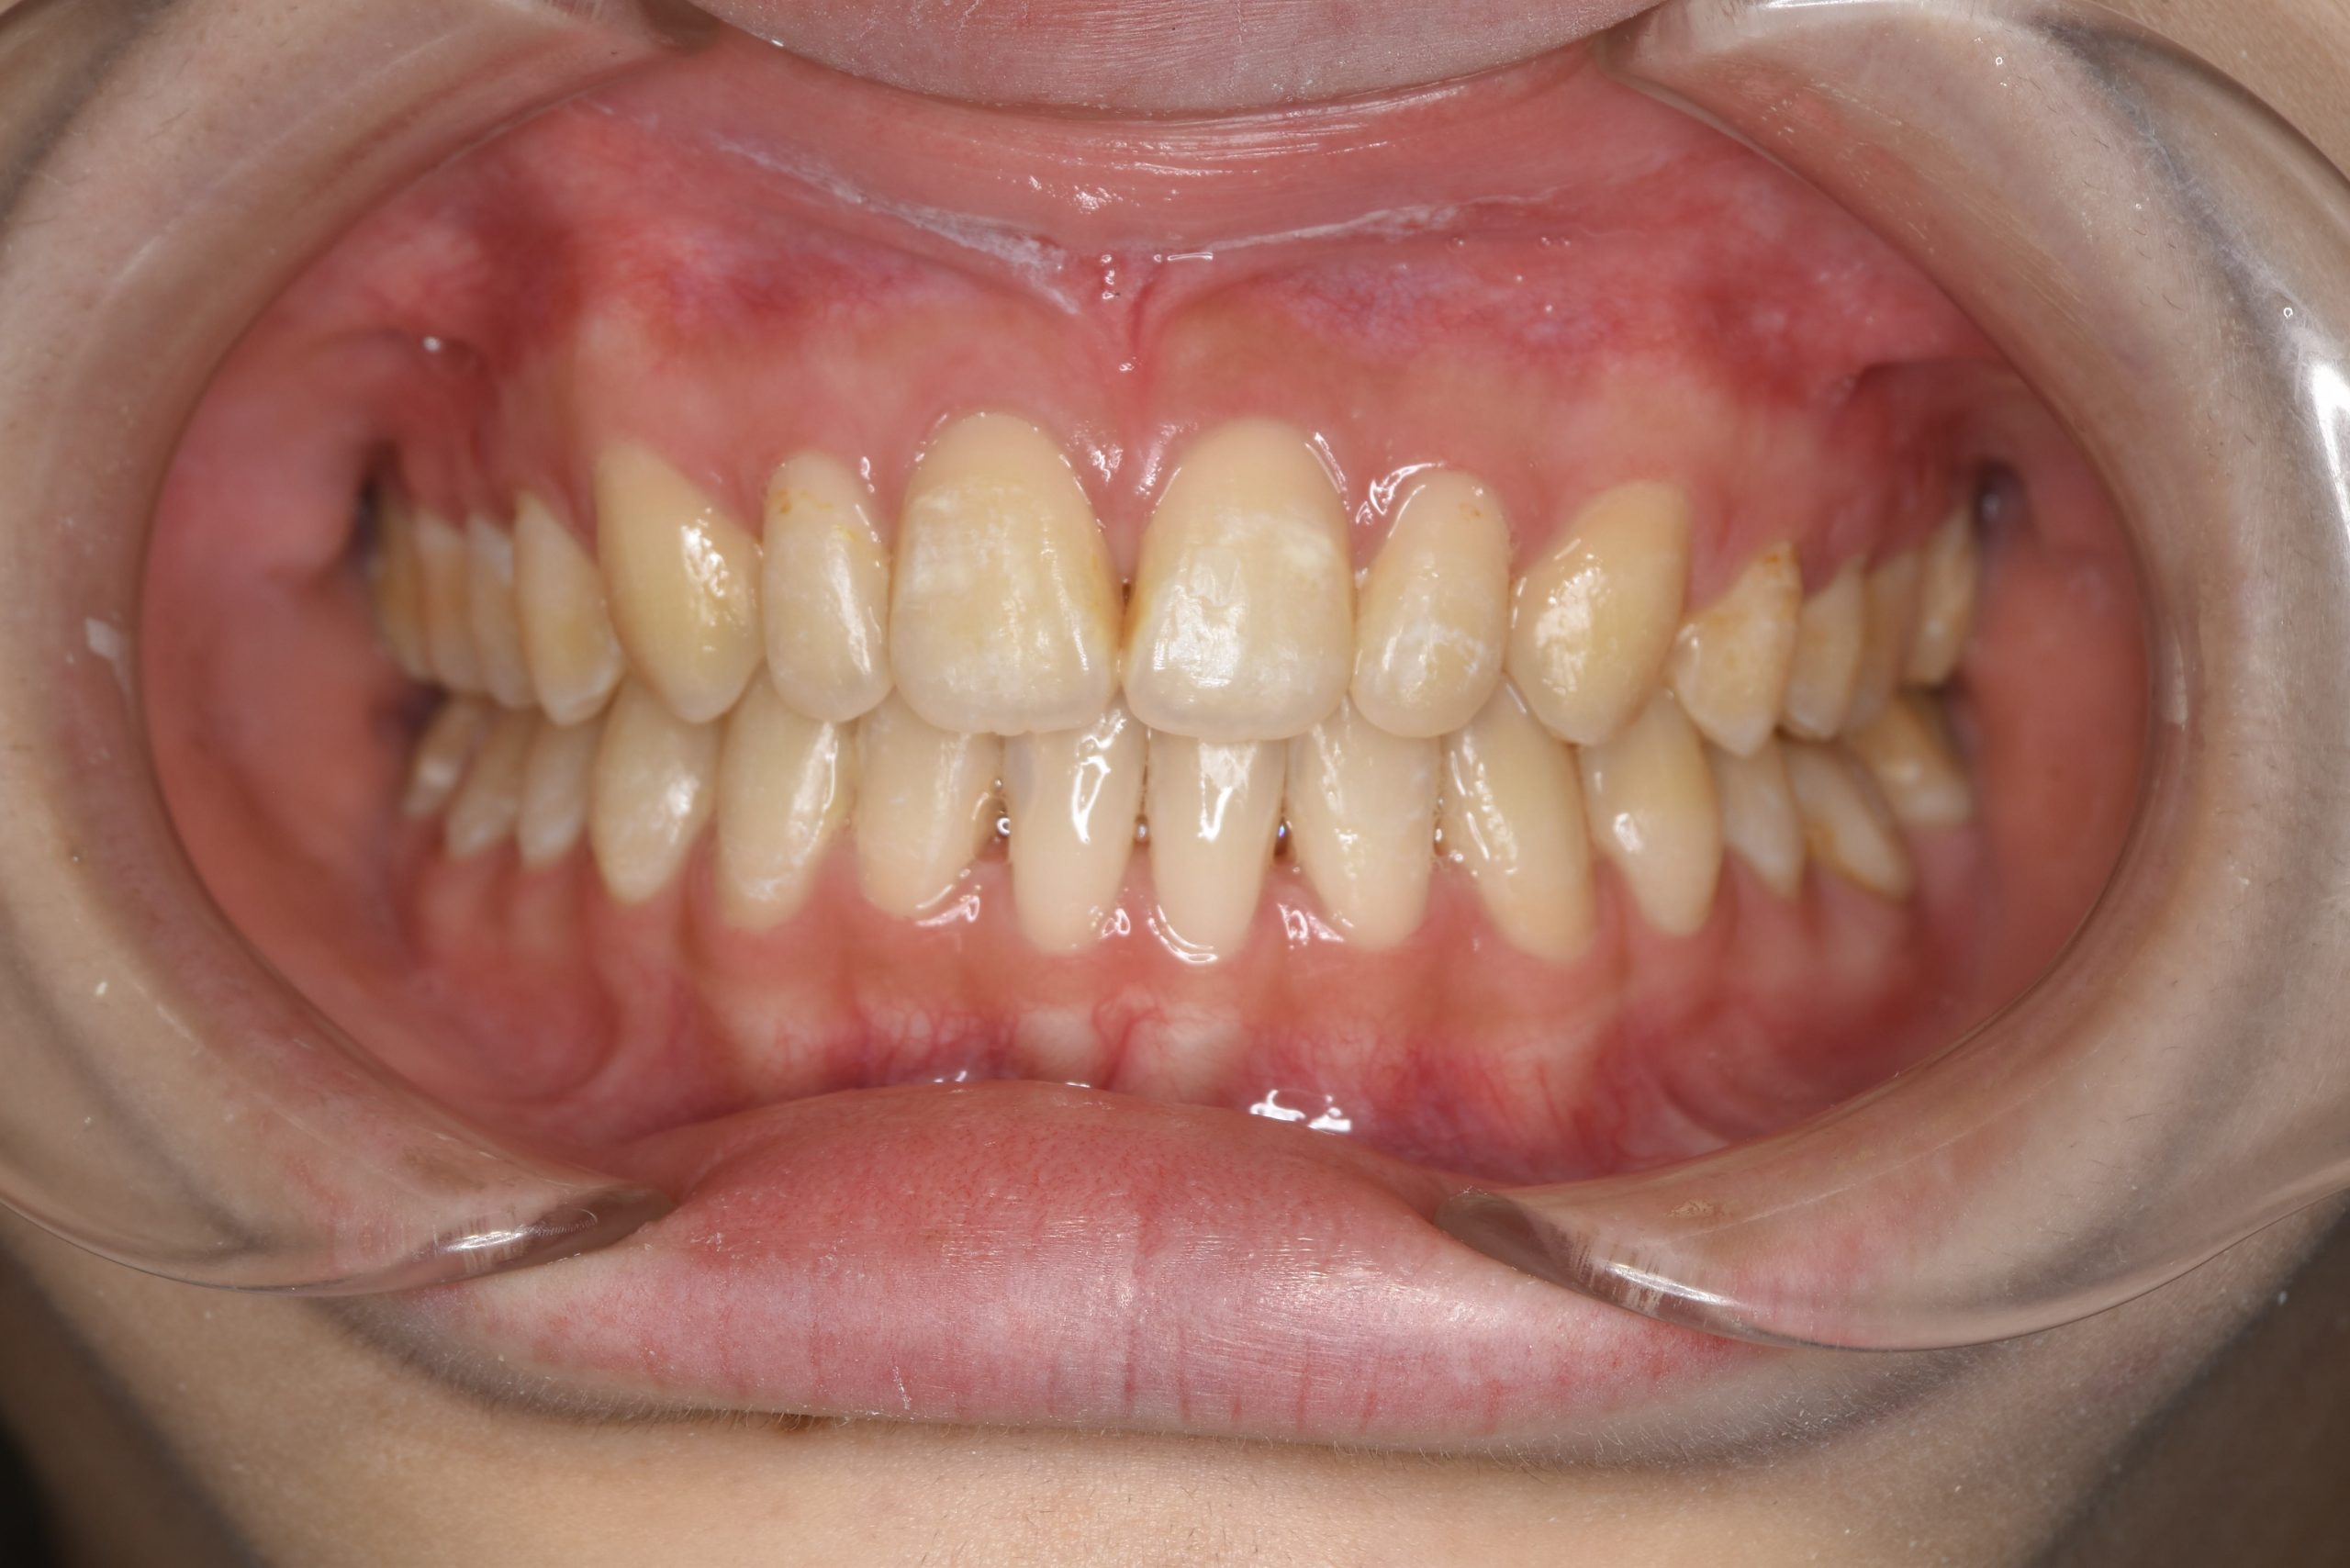

アフター

ワイヤー矯正治療|症例_032

施術内容 MSEと下顎リンガルアーチを用いて上下顎骨を拡大した。

その後マルチブラケット装置を用いて非抜歯で歯牙を配列し良好な咬合を獲得した。

吸指癖と鼻閉症状は改善した。

治癒期間 2年2か月間